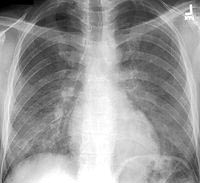

Thể hô hấp

Ở phổi, có biểu hiện: ho, đau ngực do viêm màng phổi, tràn khí màng phổi, tràn dịch tràn khí màng phổi, bệnh nhân có thể khạc ra giun[[12].